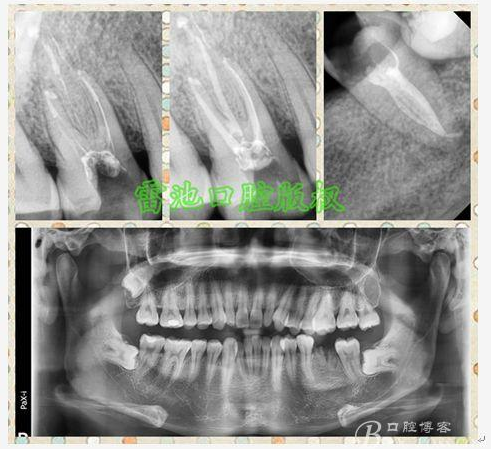

E 、X線影像學(xué)的檢查研判能力: 這點(diǎn)不需要強(qiáng)調(diào)太多,對(duì)于普通的非CBCT的二維影像對(duì)醫(yī)生讀片能力有一定的要求,有個(gè)逐步提高的過(guò)程,非一蹴而就,需要學(xué)會(huì)把二維的X線影像與三維的解剖結(jié)構(gòu)進(jìn)行良好的對(duì)應(yīng)結(jié)合,對(duì)于某些鈣化的髓室底,應(yīng)通過(guò)想象把根管口的分布、根管的走向以及各種變化通過(guò)想象投射到對(duì)應(yīng)的髓室底上;

H、關(guān)于下磨牙MM根管的重視問(wèn)題: